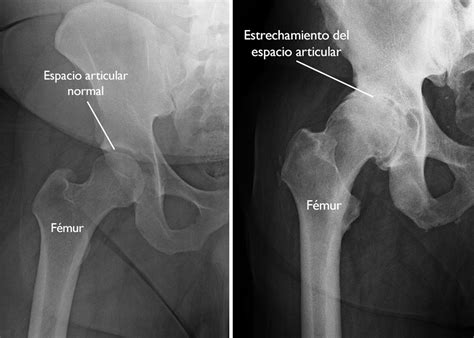

Artrosis de cadera is a progressive disease that primarily affects the hip joint. The hip joint is a ball-and-socket joint, where the head of the femur (thighbone) fits into the acetabulum (socket) of the pelvis. The cartilage that lines the surfaces of these bones provides a smooth, low-friction surface for movement. Over time, this cartilage can wear down, leading to bone-on-bone contact and the characteristic symptoms of artrosis de cadera.

• Imaging Tests: X-rays, MRI, or CT scans to visualize the hip joint and assess the extent of cartilage damage.

• artrosis de cadera radiografía